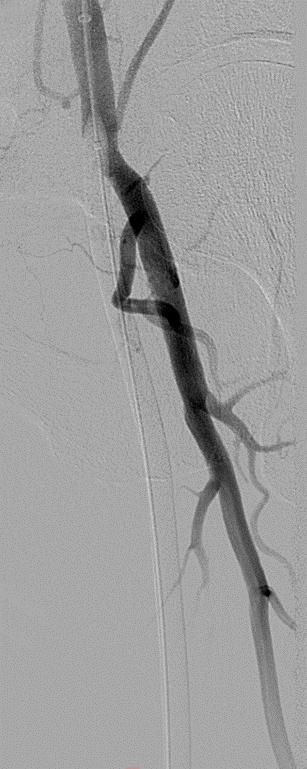

开通:以内膜下技术为主,逆穿是常用且有效的辅助手段。

预扩:充分预扩张至关重要,需逐级使用高压球囊,最终达到 6mm 直径,以获得足够的管腔。

支架植入:遵循“由远及近”原则,先放置远端 DES,再覆盖中段 VB,最后处理近端。利用 Eluvia 的可调节性优化重叠。

后扩:常规使用 6mm 高压球囊进行后扩张,确保支架充分贴壁和管腔获得。